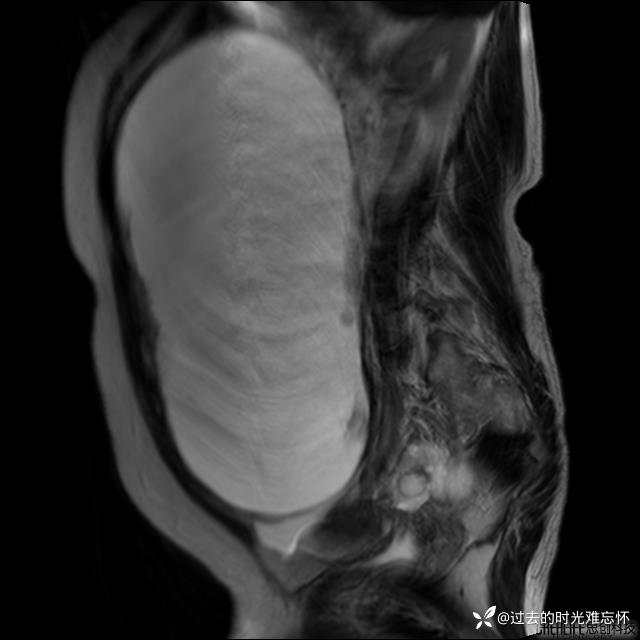

腹大能容5000液;术后腹部好轻松。妙手回春有结果。公布结果。

患者性别:女

患者年龄:65岁

主诉: 发现腹部隆起半年余。无其他明显不适。

浆液性囊腺瘤 (22)